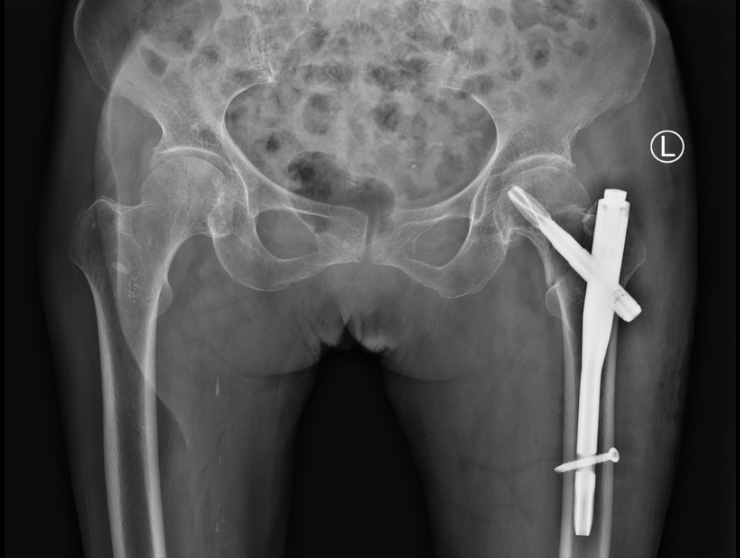

2022年10月,96岁的石奶奶在家走路时不慎摔倒造成“左侧髋部股骨转子间粉碎性骨折”而剧烈疼痛、无法站立,连卧床翻身都极为困难,我院成功施行微创接骨治疗了石奶奶的粉碎性骨折(骨折闭合复位髓内针固定术)。

术前